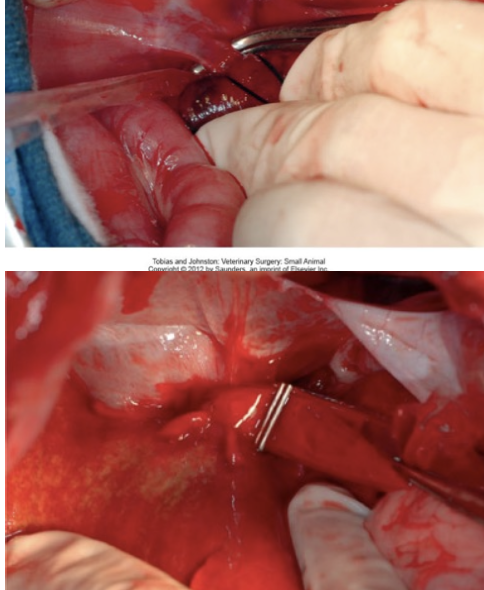

How are cholecystectomies performed?

- Ensure patency of CBD (bile needs to be able to get from liver to intestines)

- Dissect free from fossa

- Double ligate cystic duct

- Ligate cystic artery

How is the patency of the CBD assessed/maintained?

- Choledochal catheterization and stenting

- Catheterization can be normograde or retrograde (Incision into duodenum and threading through major duodenal papilla) and followed with flushing

- Stenting involves placing a red rubber in the CBD which is sutured to the duodenum aborally to the major duodenal papilla (the animal will poop it out with time)